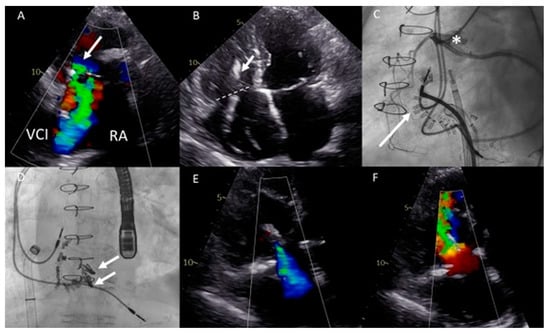

(A) Color Doppler apical four-chamber view shows severe tricuspid regurgitation (TR) with a wide vena contracta (arrow) and a systolic jet reaching the roof of the enlarged right atrium (RA). (B) Color Doppler showing turbulent inflow through the tricuspid valve (TV) bioprosthesis and aliasing, mean gradient was elevated at 4–5 mmHg. (C) Continuous wave Doppler showing a dense TR signal with low velocity. (D) Calcified and degenerated tricuspid bioprosthesis (arrow). (E) Axial slice through a computed tomography (CT) scan at the level of the right ventricle shows a giant RA and an intra-atrial septum deviation towards the left atrium (arrow), partially suppressing it. (F) Sagittal CT slice shows the inflow angle of the inferior vena cava-right RA and the RA-TV. Note the distended hepatic vein (HV). (G,H) Right anterior oblique fluoroscopy projections show the expansion of the Sapien 3 valve (asterisk) using the ring of the degenerated bioprosthesis as the reference and the final result, respectively. (I,J) Apical four-chamber color Doppler views showing normal function of the valve-in-valve bioprosthesis (appreciate the difference with (A,B), respectively). (K,L) View of the valve-in-valve bioprosthesis in systole (closed) and diastole (open), respectively.

This was successfully performed under local anesthesia, by means of right femoral access and fluoroscopy and TTE guidance. A temporary pacemaker wire was placed in the left ventricle and the AgilisTM steerable introducer (Abbott, IL, USA) was used to safely access the RA, given the relatively sharp angle between the vena cava-RA and the RA-RV axis (Figure 4F). The Edwards eSheath TM (Edwards Lifesciences, USA) was then used to implant a 29 mm Edwards SAPIEN 3 valve (Edwards Lifesciences) in the TVR bioprosthesis under rapid pacing (Figure 4G,H). Normal function of the new valve-in-valve bioprosthesis was confirmed by transthoracic echocardiography (Figure 4I–L). The periprocedural course was uneventful. At 22 months follow-up, the patient is in NYHA functional class I with moderately reduced (yet significantly improved) RV function and normal function of the bioprosthesis.